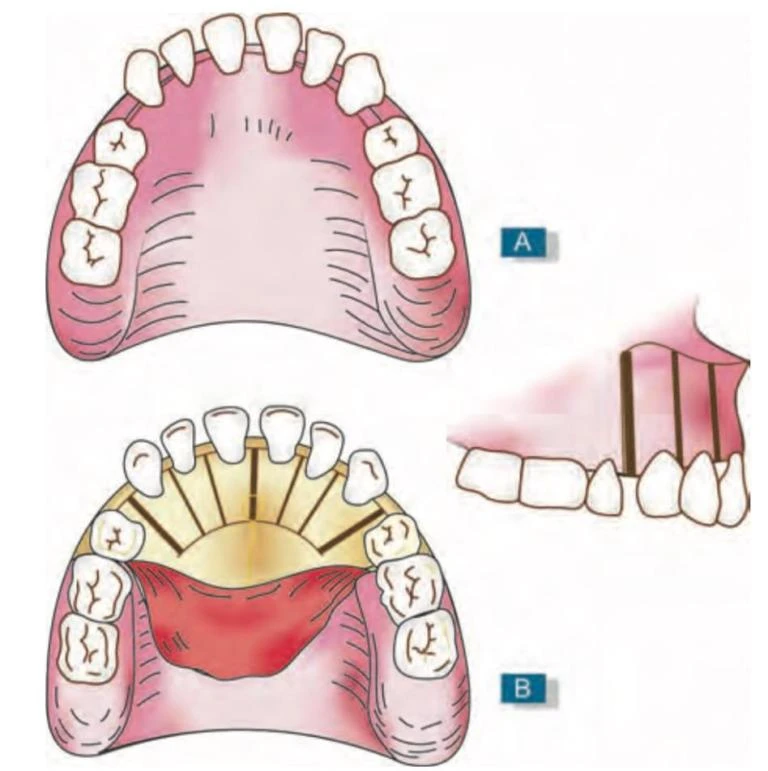

Kỹ thuật

Lật vạt rộng ở mặt ngoài và mặt trong dưới gây tê vùng hoặc gây tê tại chỗ, để bộc lộ xương vỏ mặt ngoài và mặt trong của răng. Các vết cắt theo chiều dọc có chiều rộng đã được xác định trước được thực hiện bằng mũi khoan ở cả hai bên mỗi răng đi xoa xương vỏ song song và không chạm vào chân răng. Điểm kết thúc của những đường cắt này được nối lại bởi những đường cắt ngang qua xương vỏ, vì vậy các răng cần điều chỉnh chỉ được nâng đỡ bởi xương xốp. Đặt lại vạt và khâu. Sau 2-3 ngày, có thể gắn khí cụ chỉnh nha và đạt được di chuyển răng nhanh. Cần mang hàm duy trì 6 tháng để ổn định kết quả.